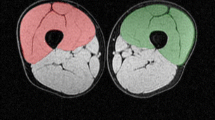

Ultrasound images were analyzed in randomized order by tracing the contours of each four of the hamstring muscles (BFlh, BFsh, ST, SM) at each ROIs using Image J, a public domain software for image analysis (https://imagej.nih.gov/ij/). Once CSAs measurements were obtained at the specific ROIs along the muscle length, by knowing the distance between the different ROIs (constant, as they were identified as percentages of the total femur length), muscle volume (VOL) was calculated for each muscle (for the portion between 30 and 60% of whole femur length) using the truncated cone formula27,28:

All MRI data were acquired on a 3T scanner (Magnetom Prisma, Siemens, Erlangen, Germany). Participants were positioned supine on the MR system's patient bed, fitted with ear protection, and instructed regarding the use of the alarm bell and scans, followed by the acquisition of localizer scans. After ca. 5 min that allowed for body fluid shift stabilization, up to three spatially overlapping T1w spoiled 3D gradient echo data sets of both thighs were acquired in the axial (transverse) orientation and combined into a single image series. Acquisition parameters: sequence: vibe, TR/TE: 3.23/1.23 ms, flip angle: 15°, field of view: 450 × 337.5 mm, encoded nominal voxel size: 1.3 × 1.3 × 3 mm, no inter-slice gap, readout-bandwidth 790 Hz/pixel (278 kHz), acquisition time per 3D volume: 1 min 23 s. In the corresponding images, contours of the semimembranosus (SM), the semitendinosus (ST), and the biceps femoris long (BFlh) and short heads (BFsh) muscles were digitized in randomized order using the Merlin Diagnostic Workcenter DICOM image analysis software (Phönix-PACS GmbH, Version 5.3.156494, https://www.phoenix-pacs.de/image-display/) (Fig. 1). As for the US technique, once CSAs measurements were obtained at the specific ROIs along the muscle length, muscle volume (VOL) was calculated using the truncated cone formula27,28 for each muscle (for the portion between 30 and 60% of whole femur length).